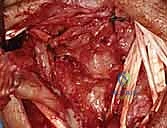

3. Capsulotomy and Joint Exposure

Now, we'll open the dorsal wrist capsule to inspect the carpal joints and the LT ligament directly.

- Ligament-Splitting Capsulotomy: We'll perform a dorsal ligament-splitting capsulotomy, as described by Berger and Bishop. This approach is preferred because it preserves the integrity of the crucial dorsal radiocarpal and intercarpal ligaments, which are important secondary stabilizers.

- Identify Key Ligaments: First, identify the dorsal radiocarpal ligament (specifically the dorsal radiotriquetral ligament) and the dorsal intercarpal ligament. These form a "V" shape on the dorsal aspect of the wrist.

- Incision: The capsulotomy incision is made between these two ligaments, splitting the capsule longitudinally.

* Reflection: Carefully reflect the dorsal capsule radially and ulnarly, creating two flaps. Use fine stay sutures or small skin hooks to retract the capsule, providing excellent visualization of the underlying carpal bones and ligaments.

- Joint Inspection: With the capsule opened, we can now directly visualize the midcarpal and radiocarpal joint surfaces. Take a moment to thoroughly examine these for any arthritic changes, chondral damage, or other intercarpal pathology that might influence our repair strategy.

Now, direct your attention specifically to the **scapholunate and lunotriquetral ligaments**. Thoroughly examine the dorsal aspect of the lunotriquetral ligament. Assess its integrity, quality, and whether it appears suitable for direct repair. We're looking for clean tears that can be reapproximated versus attenuated, frayed tissue that would necessitate reconstruction. Perform dynamic stress tests under direct visualization to confirm the degree of instability.